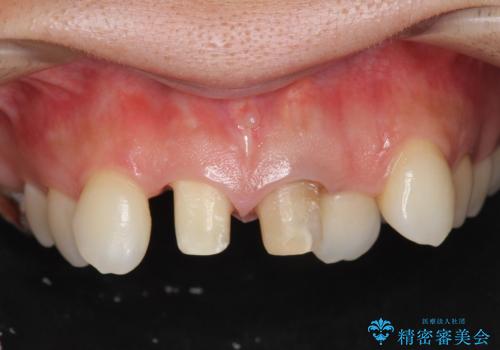

子供の頃にぶつけた前歯 根管治療から行うセラミック治療

- 幼少時にぶつけ、神経を取った歯の審美改善を求めて来院されました。

X線写真より不十分な根管治療、根尖病変、前歯の変色が認められます。

歯根の近接のみられる右上側切歯を抜去し、根管治療を伴うセラミック治療を計画します。